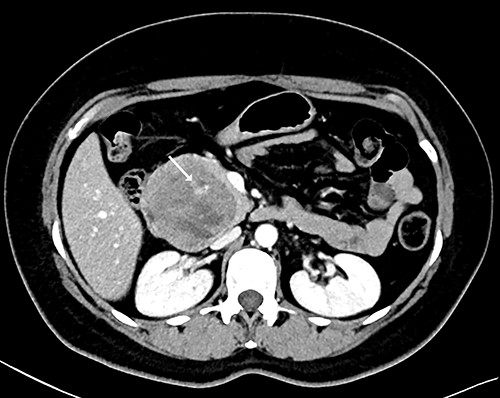

Our patient is a 44-year-old healthy female who presented to the emergency department with a 1-week history of epigastric pain associated with melena, fatigue and dizziness. The abdomen was soft without tenderness, and the laboratory test showed haemoglobin at 7.3 g/dL. After two units of red blood cell transfusion, she underwent an emergency endoscopy. A 2 cm bleeding ulcer was found in the duodenal bulb with jagged edges and an adherent clot (Fig. 1). Epinephrine injection and argon plasma coagulation were used to achieve haemostasis. A CT scan revealed a well-defined heterogeneous 6.7 cm mass with solid and cystic components arising from the head of the pancreas and the enhancement of contrast in the solid component (Fig. 2). No dilatation of the common bile duct or pancreatic duct was noted. The patient was discharged without signs of bleeding and haemoglobin at 10.4 g/dL. Biopsy samples of the duodenal ulcer showed chronic inflammation, and some glandular structures suspicious of neoplasia.

CT scan showing a well-defined heterogeneous 6.7 cm mass with solid and cystic components arising from the head of the pancreas with enhancement of contrast in the solid component, and some areas with active bleeding (white arrow). The tumour was in direct proximity to the duodenum.